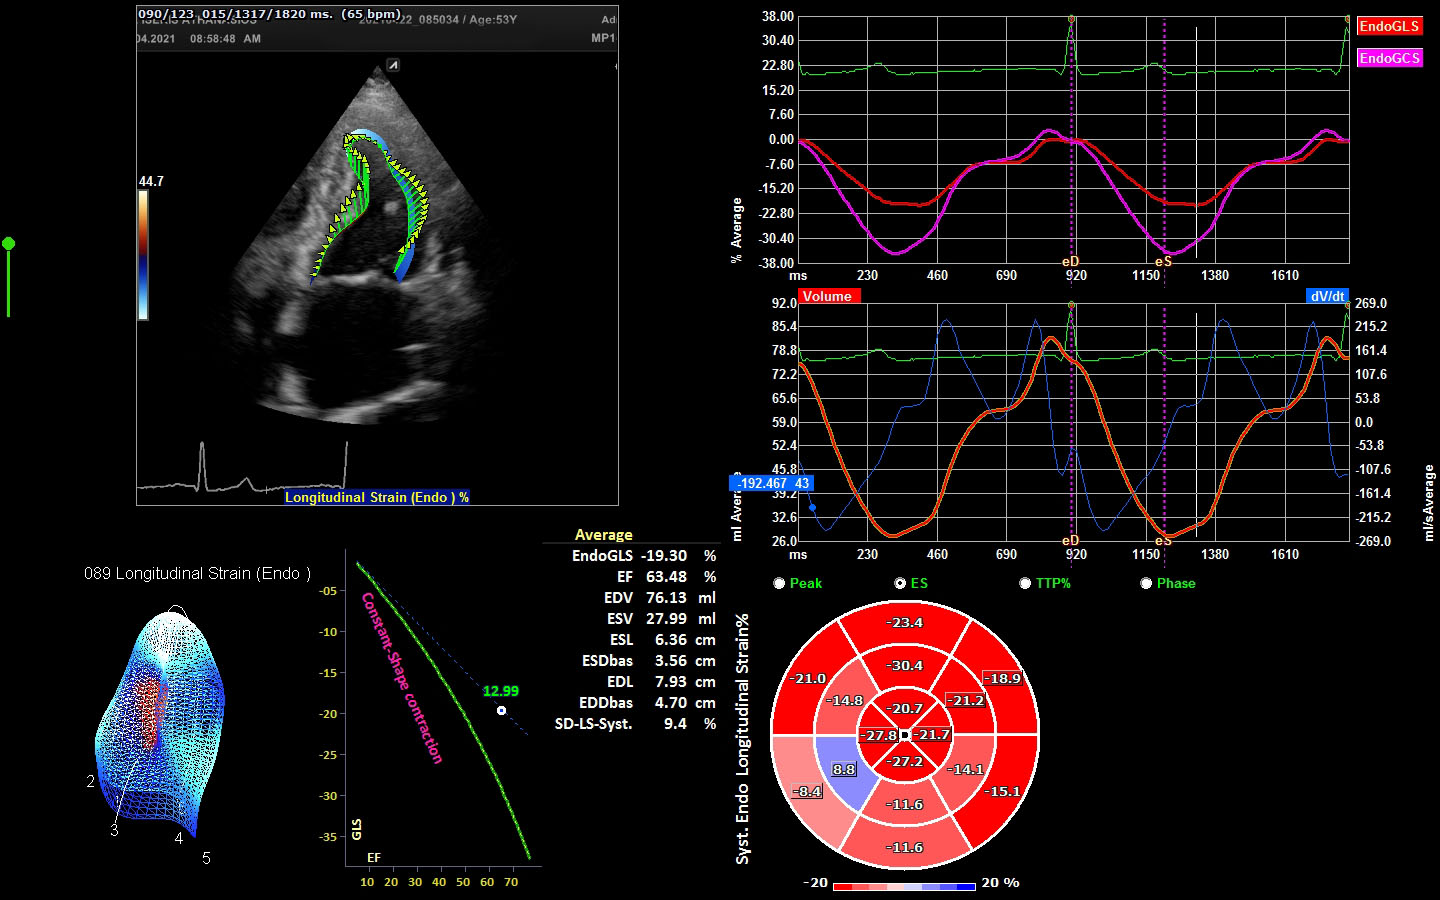

Μελέτη ιστικής παραμόρφωσης (myocardial strain)

Στο ιατρείο μας έχουμε τη δυνατόητα εφαρμογής νεότερης τεχνολογίας υπερηχογραφικών τεχνικών (longitudinal strain) που αυξάνουν κατά πολύ την διαγνωστική αποτελεσματικότητα. Το λογισμικό αναλύει την λειτουργία της καρδιάς και εντοπίζει τμηματική και συνολική δυσλειτουργία που δεν ειναι εμφανής στο γυμνό μάτι.

Εξειδικευμένη εξέταση μελέτης ιστικής παραμόρφωσης

H εξέταση γίνεται με εφαρμογή νεότερης τεχνολογίας υπερηχογραφικών τεχνικών (longitudinal strain) που αυξάνουν κατά πολύ την διαγνωστική αποτελεσματικότητα.